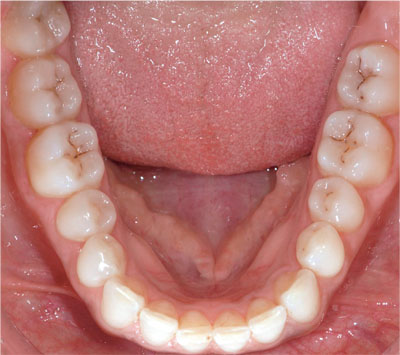

As a consequence of increased dental awareness in society, coupled with improvements in dietary and oral hygiene practices, many more patients, particularly younger patients, are now presenting with fewer and smaller lesions of caries than in the past (Figs 1-1 and 1-2). Such patients expect minimally interventive procedures, preferably using techniques that are described as “aesthetic” or “tooth coloured” (Fig 1-3). This, in association with commercial developments in composite resin materials and associated bonding technologies and lingering concerns over the safety of dental amalgam, has driven an increase in the placement of posterior composite restorations in general dental practice. For example, a survey of United Kingdom general dental practitioners in 2001 revealed, far from limiting the placement of composite to small cavities in premolar teeth, that almost one-half of general dental practitioners placed composite resin restorations in load-bearing cavities in molar teeth (Figs 1-4 to 1-6).

Fig 1-1 Mandibular dentition from a 30-year-old female, which is unrestored and caries free, albeit with some staining of occlusal fissures.